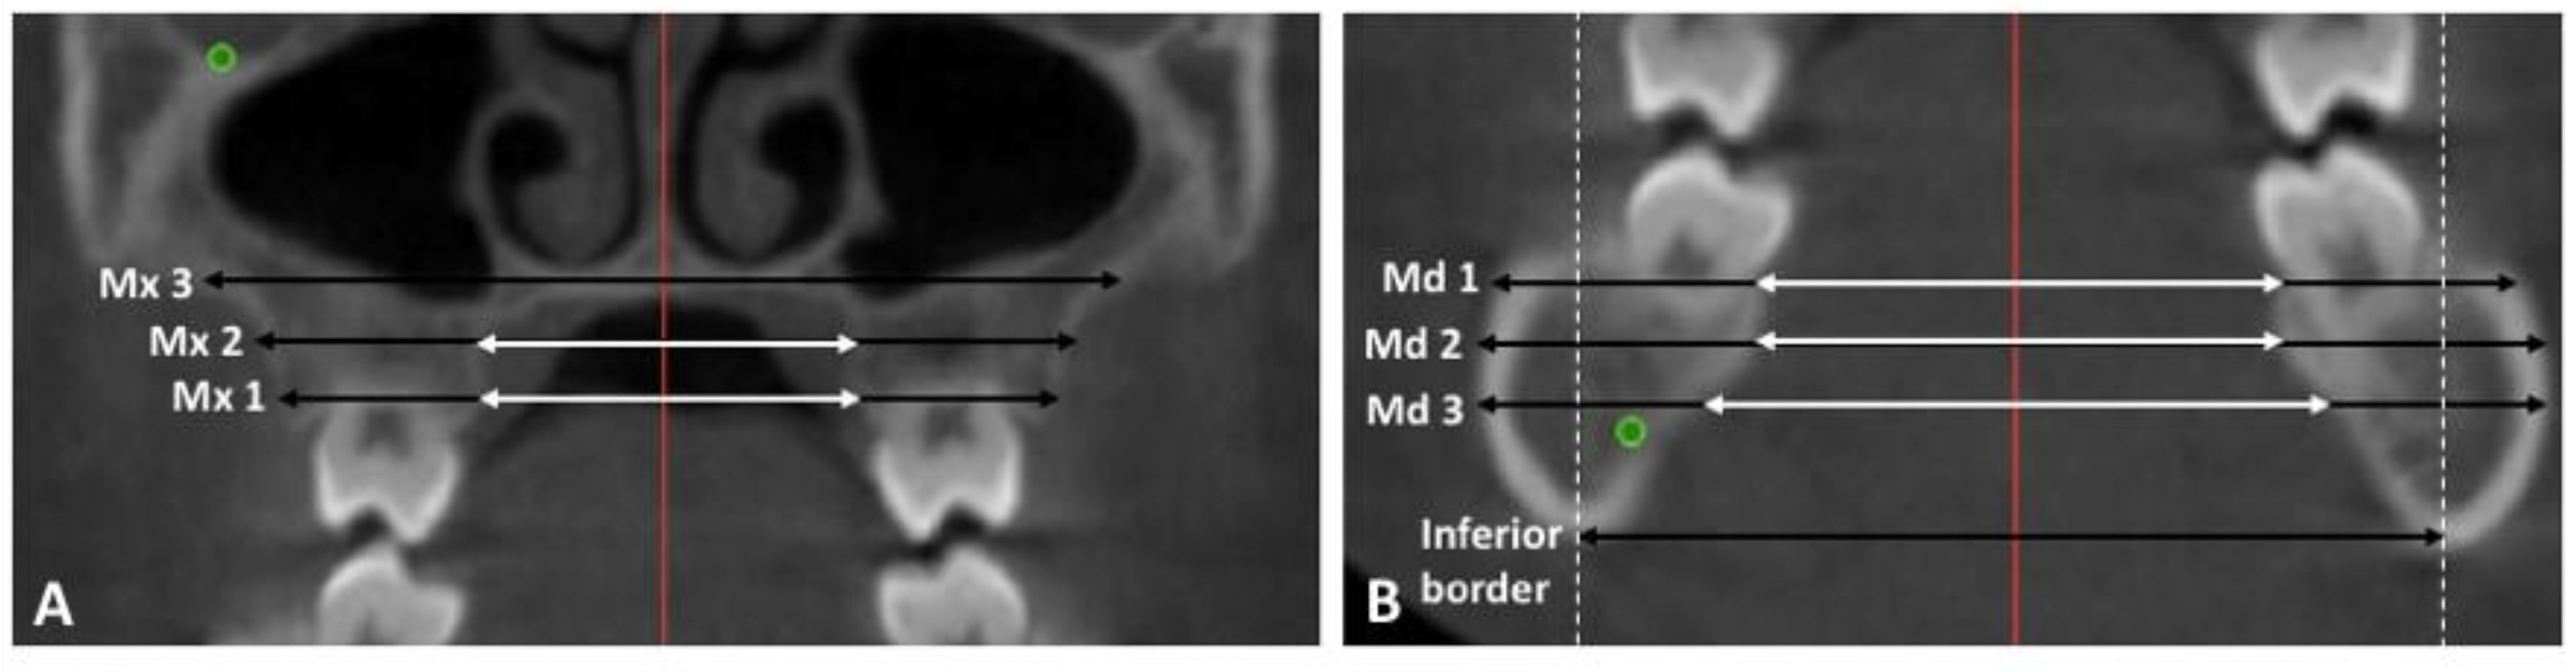

- Mx 1: 2 mm apical to the U6 CEJ on the T1 image. The most coronal axial cut on the T2 image.

- Mx 2: 6 mm apical to the U6 CEJ on the T1 image. The mid-axial cut between the most coronal and most apical cut on the T2 image

- Mx 3: 10 mm apical to the U6 CEJ on the T1 image. The most apical axial cut on the T2 image.

- Md 1: 2 mm apical to the L6 CEJ on the T1 image. The most coronal axial cut on the T2 image.

- Md 2: 6 mm apical to the L6 CEJ on the T1 image. The mid-axial cut between the most coronal and most apical cut on the T2 image

- Md 3: 10 mm apical to the L 6 CEJ on the T1 image. The most apical axial cut on the T2 image.

- Mandibular inferior border: the most inferior point on the mandibular border identified on a coronal section.